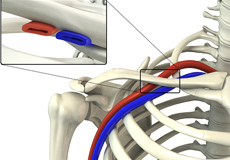

Thoracic Outlet Syndrome

The thoracic outlet is a small passageway leading from the base of the neck to the armpit and arm. This small area contains many blood vessels, nerves, and muscle.